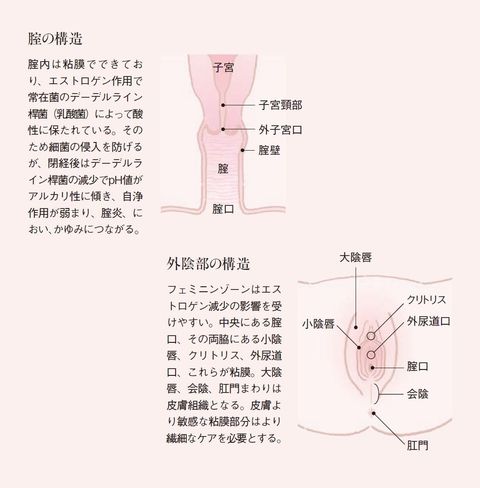

女性器について 正しい知識を持ちましょう ゆかりレディースクリニック 神戸市三宮にある婦人科

会陰 えいん は 腟口 ちつこう から肛門までを指します。 生殖器は発生学的由来により内生殖器と外生殖器に分けられます。外陰部は体表の皮膚が変化して生じた外生殖器で、外からの刺激に対して生殖器を守る役割があります。会陰部に近いほど男性化不全の程度が強い 4.陰嚢の形成は? 低形成、二分陰嚢の有無 <Quigley分類> 完全男性型 完全女性型 図:たのしく学ぶ小児内分泌より 外陰部の診察:女児の男性化 1.陰核の大きさは? 横径を計測することが多い。 >7 mm → 陰核肥大 2.膣口は確認できるか? 3.陰唇動画あり出張オイルリンパマッサージの四ツ目本舗は東京都心部のホテル・自宅へ、深夜1時迄、出張オイルリンパマッサージを提供。「no sokeibu, no life紙パンツを捨てよう!」当店の「鼠径部(そけい部)オイルリンパマッサージ」の「会陰部について」の説明

女性器について 正しい知識を持ちましょう ゆかりレディースクリニック 神戸市三宮にある婦人科